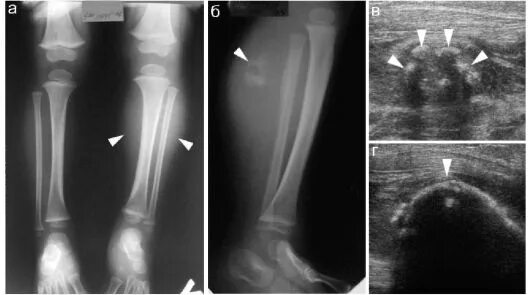

Оссифицированный миозит